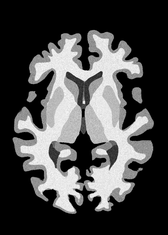

4.2 Registration to a 100 micron ex-vivo brain MRI volume

To showcase the efficacy of our method on real large scale images, we register a 250 in-vivo MRI image (Lüsebrink et al., 2017) to a 100 ex-vivo FLASH human brain volume (Edlow et al., 2019). This represents an inverse problem with more than 11.2B optimizable parameters (compared to 20M for clinical datasets), or 44.8GB of GPU memory. The entire problem does not fit on most GPUs, necessitating distributed multimodal registration. We optimize a composite transform - affine followed by a diffeomorphic mapping; details can be found in Section E.1. Multimodal deformable registration took 58 seconds on 8 NVIDIA A6000 GPUs, which is unprecedented at this resolution. Fig. 6 shows qualitative results, highlighting the ability to register highly detailed structures such as cerebellar white matter; these structures are not visible at macroscopic scales. The resultant advantages of performing registration at this scale can allow researchers to characterize the neuroanatomy at microscopic resolutions and allow morphometric analysis of cortical layers and subcortical nuclei among other structures.